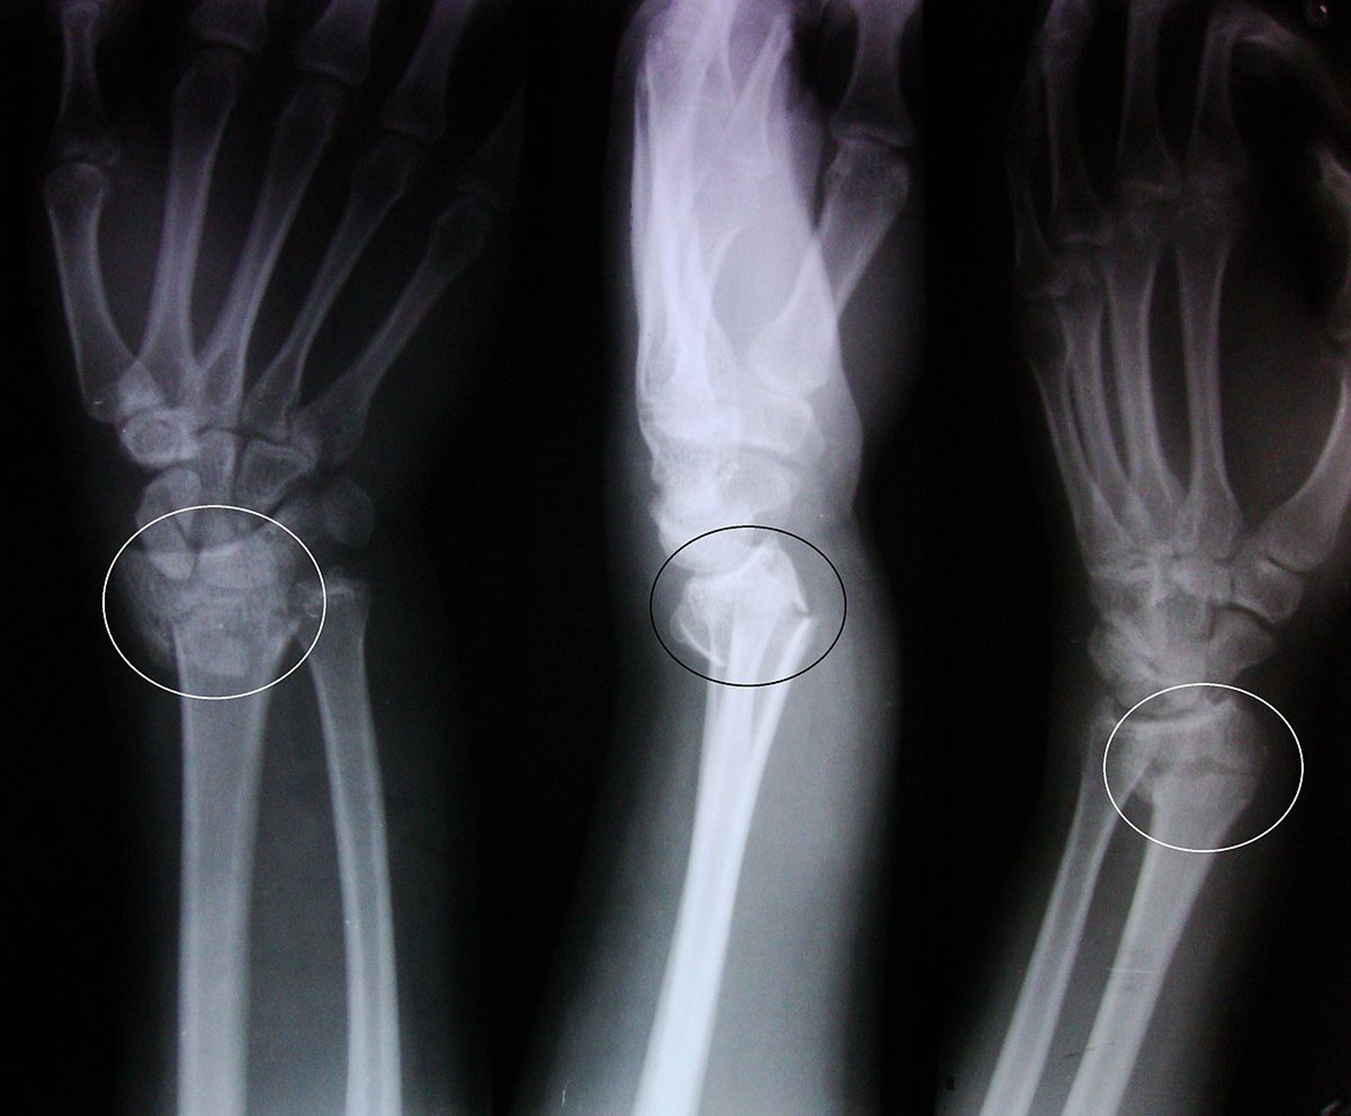

What fx is this

Colles’ fx